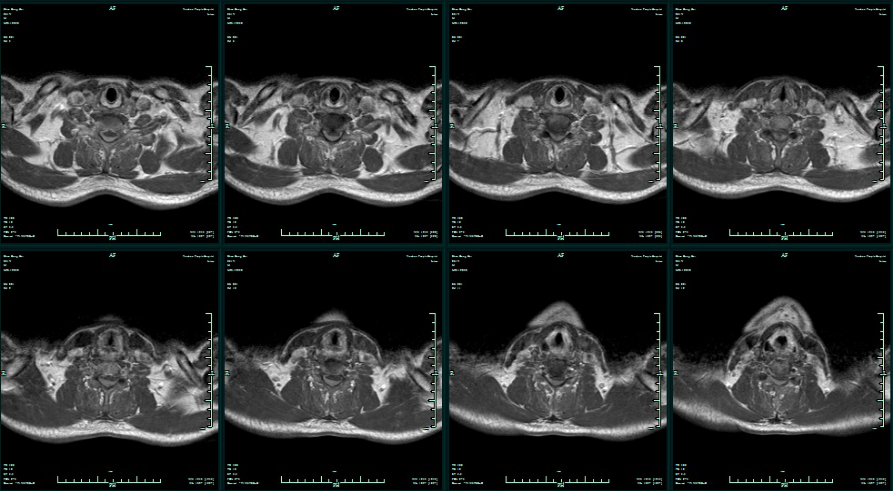

术后3个月,出现双手活动稍不便,行走稍有不稳,查双手肌力左V-级,右IV级。复查MR增强示病灶复发,(手术部位无病灶生长,脊髓腹侧周围可见病灶生长。)

术后3月颈椎MR增强

治疗2周后再次复查MR增强